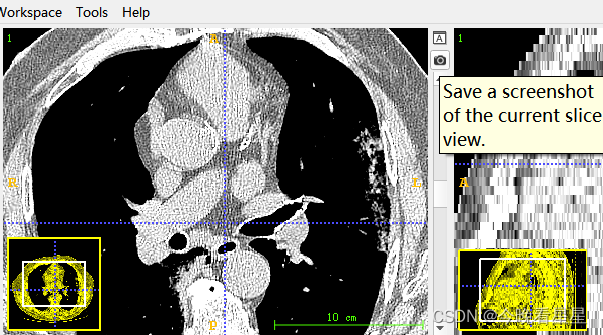

- 对当前进行截图

Image Slice单对切面的导出,导出的格式为png, 不包含标注的图像Screenshot / Screenshot Series将图片导出为截图的格式,包含了图片的标注信息。与导出切片不同,导出的截图与图像在软件中的显示是一样的,常用于一些图像的说明